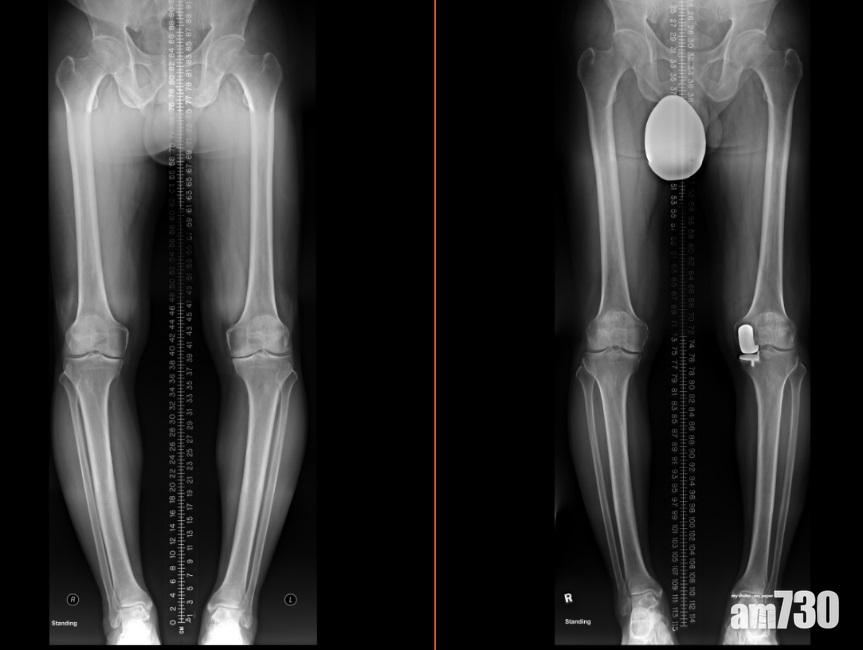

半膝關節置換(右)保留了健康的組織,患者康復後走路的姿勢更自然。(圖片由醫生提供)